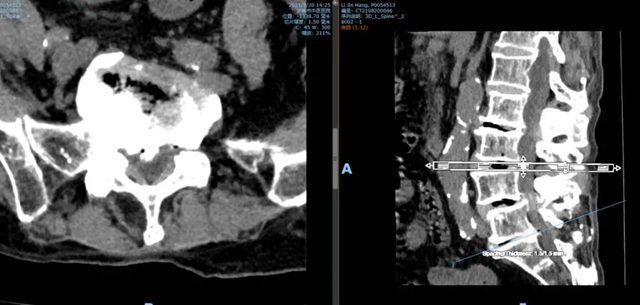

腰5骶1椎间盘CT